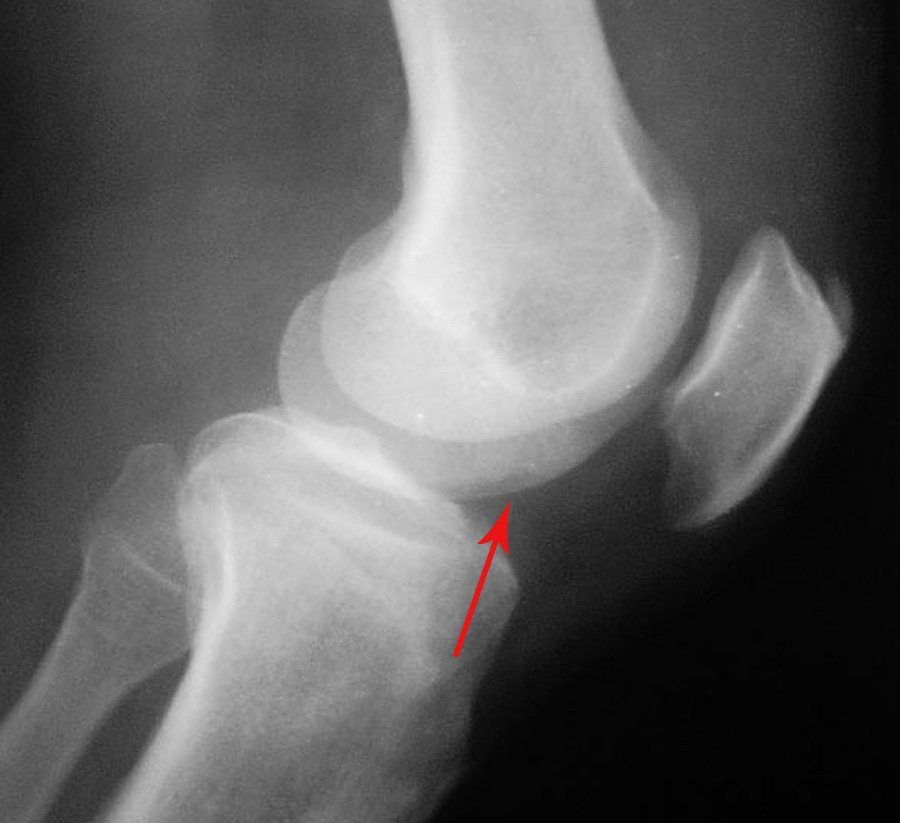

1髌骨前上缘骨刺。

1髌骨前上缘骨刺

1.左股四头肌肌腱钙化;

左髌骨前上方股四头肌]韧带钙化。

1、左髌骨前上方股四头肌]韧带钙化。

考虑:1、左侧股骨内髁剥脱性骨软骨炎并股胫外侧关节间隙游离体形成;

2、髌骨前上缘股四头肌腱骨化。